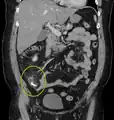

| A fecalith marked by the arrow which has resulted in acute appendicitis. | |

A fecalith is a stone made of feces. It is a hardening of feces into lumps of varying size and may occur anywhere in the intestinal tract but is typically found in the colon. It is also called appendicolith when it occurs in the appendix and is sometimes concurrent with appendicitis.[1] They can also obstruct diverticula. It can form secondary to fecal impaction. A fecaloma is a more severe form of fecal impaction, and a hardened fecaloma may be considered a giant fecalith. The term is from the Greek líthos=stone.[2]

A small fecalith is one cause of both appendicitis and acute diverticulitis.